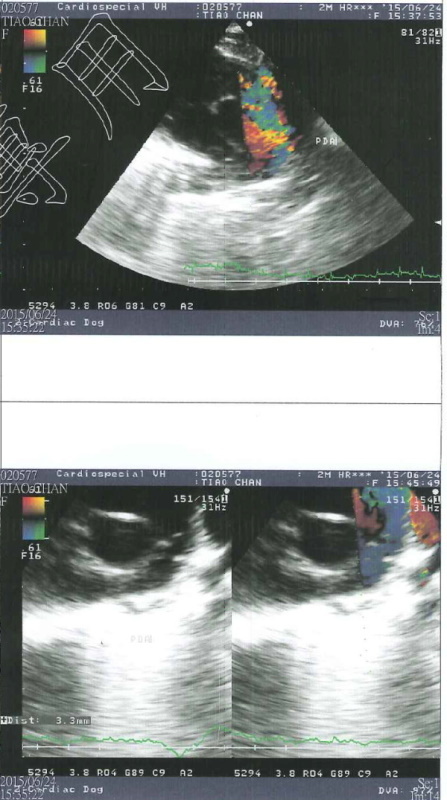

而幸運長大的三隻小奶貓分別取名貂蟬、圓圓、西施,而六月天氣變化大,早上大太陽夜裡又滂沱大雨,小貓們出現鼻氣管炎的現象,張口呼吸感覺很不舒服,貂蟬由其嚴重,呼吸得很用力非常倦怠,緊急送往醫院檢查,醫師懷疑可能有心臟方面的疾病,建議轉診道心臟專科"專心動物醫院"進行心臟超音波檢查,檢查結果心跳超快已有肺氣腫情況,診斷為PDA(開放性動脈導管),開放性動脈導管是一種常見天生的心臟狀況,在母體中血流的需求與出生後不同,而在主動脈與肺動脈之間有一條相通的血管,稱為動脈導管,通常這條血管會在出生後兩三天之內關閉,而貂蟬出生之後動脈導管沒有關閉,導致血流會從大動脈轉而流向肺動脈,一般會有易倦、生長停滯、咳嗽、呼吸速率增加、喘息等等狀況,而此次鼻氣管炎使得狀況更加明顯危急,目前貂蟬住在氧氣室內,這種先天性心臟病可透過手術治療,但需至少體重要到達2公斤才可手術,心臟超音波檢查的費用還請各位幫忙。